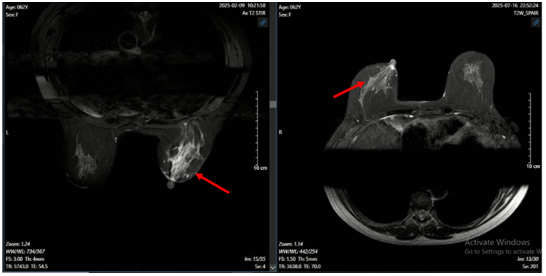

Hình ảnh MRI vú: Nhu mô góc 1/4 dưới ngoài có khối tăng tín hiệu trên T2W, giảm tín hiệu trên T1W, hạn chế khuếch tán trên DWI, ADC, bờ tua gai không đều, kích thước 19x22mm, ngấm thuốc mạnh tăng dần sau tiêm, có vài dải ngấm thuốc lan dọc ra núm vú (BIRADS 5).

Hình 2. Hình ảnh MRI vú

phải trên lát cắt ngang và đứng dọc: Tổn thương u vú được đánh dấu bằng vòng tròn và mũi tên màu đỏ.